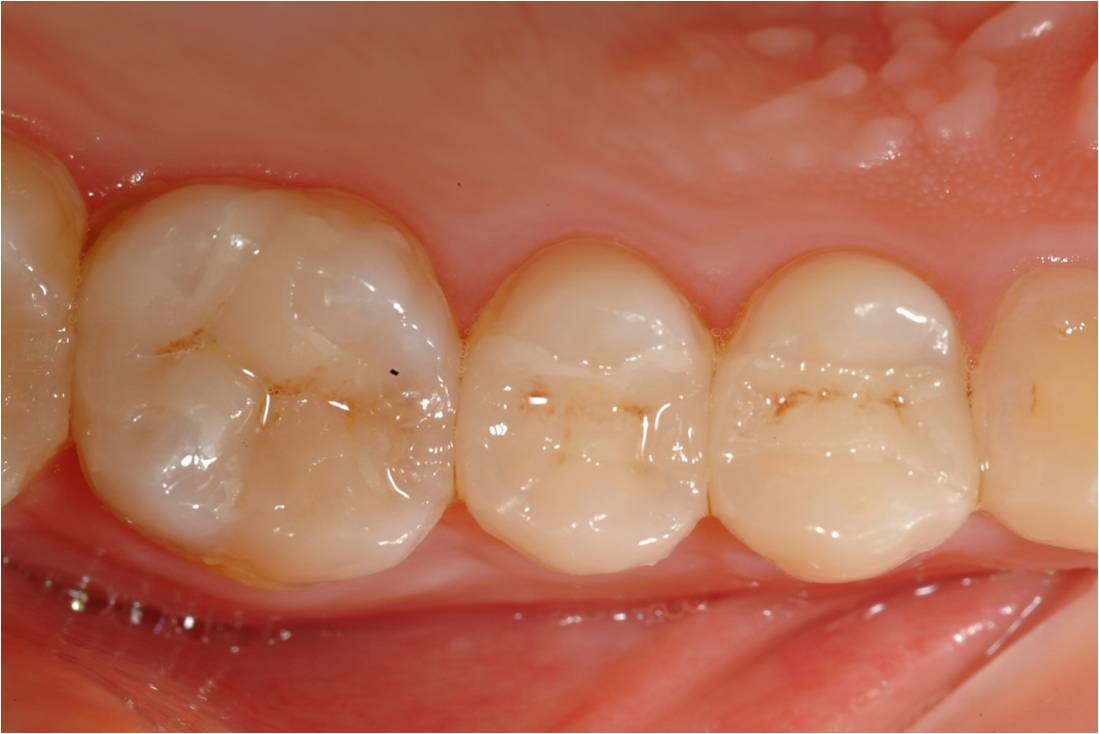

黏著後狀態

/07.jpg)

術前、術後比較